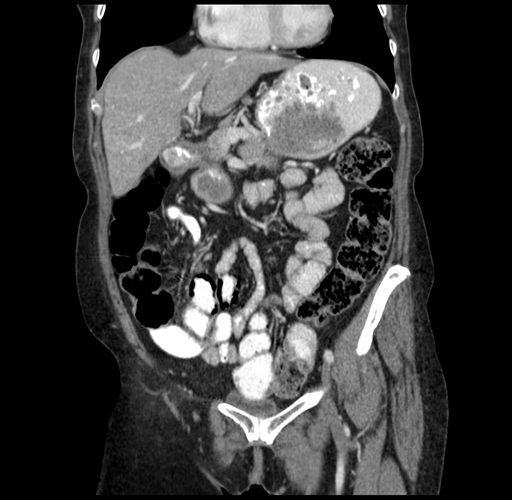

Pre-Chemo: Coronal Venous

Coronal Venous